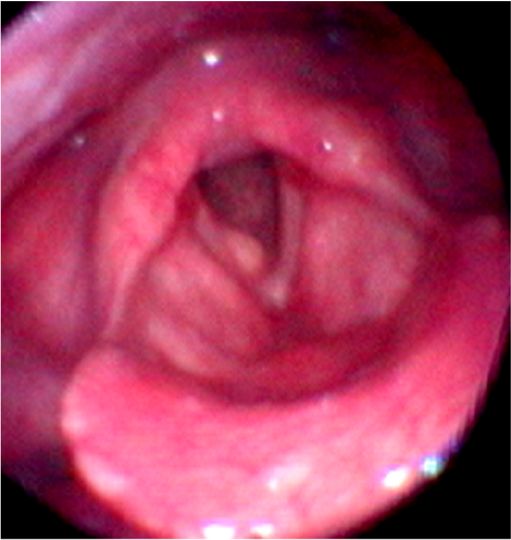

・声帯ポリープは声帯結節、声帯ポリープ、ポリープ様声帯の3種類にわけられます。

・声帯結節は声帯の前方1/3に両側性にできることが多く、小児では大声で話す男子によくみられ、成人では女性に多く発生します。

声帯結節